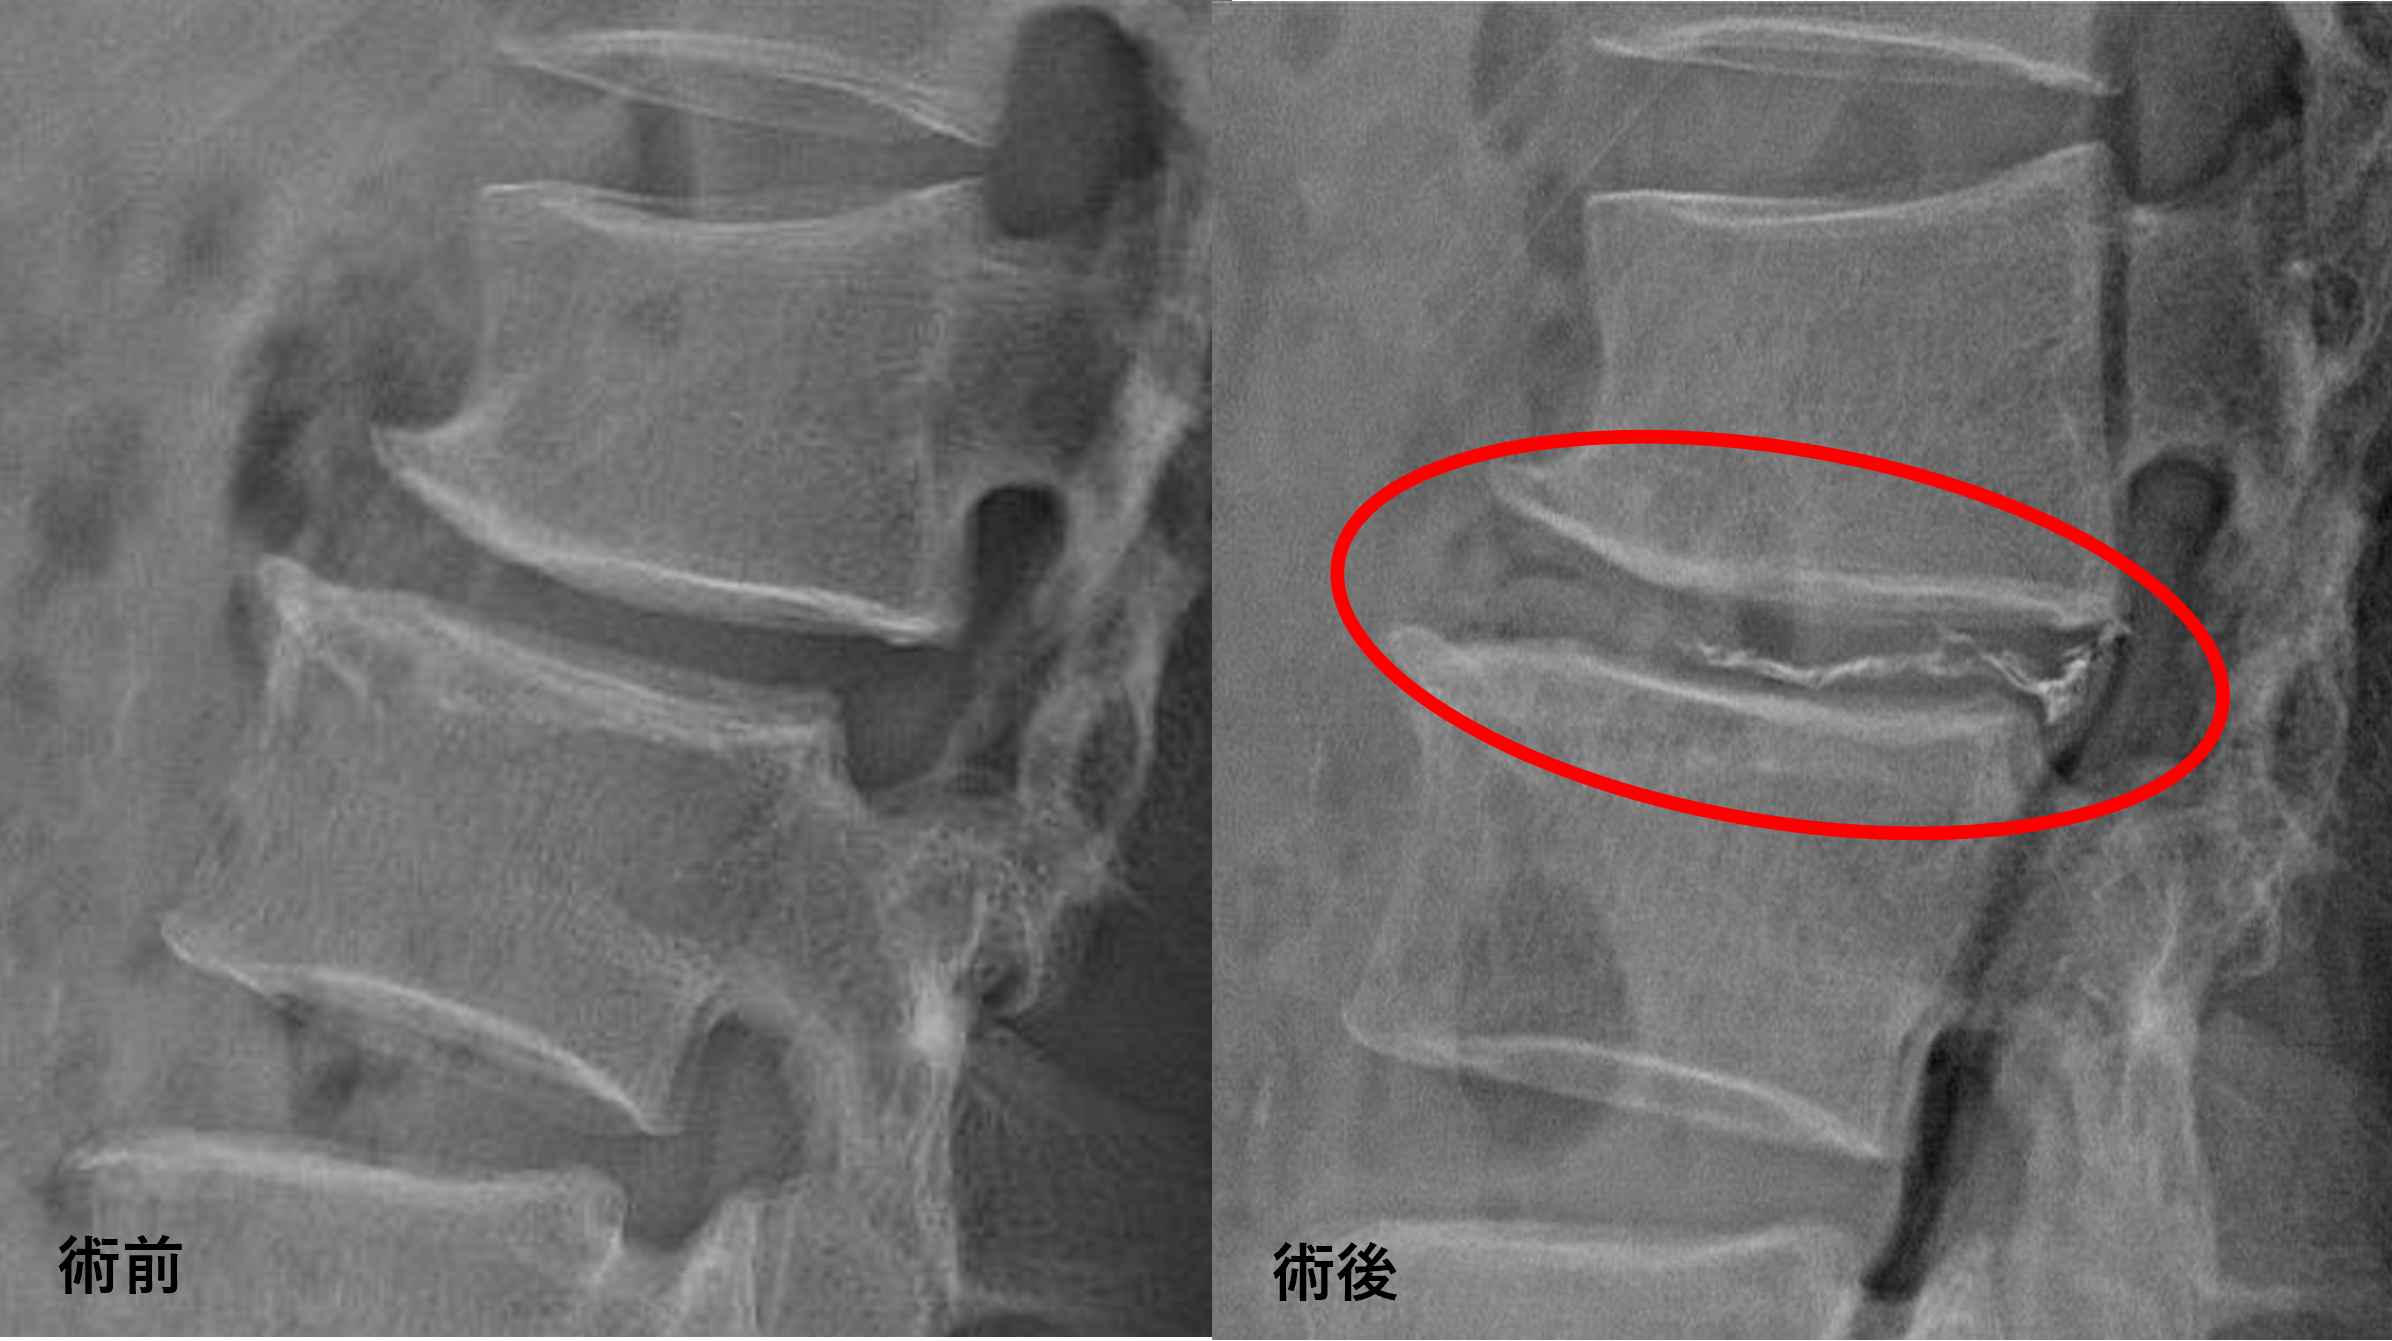

治療について

患者様と相談の元、L2/3にセルゲル法を施行

治療は小寺院長が行いました。

治療は15分程度で終了

回復室で休憩後、歩いて帰院されました。